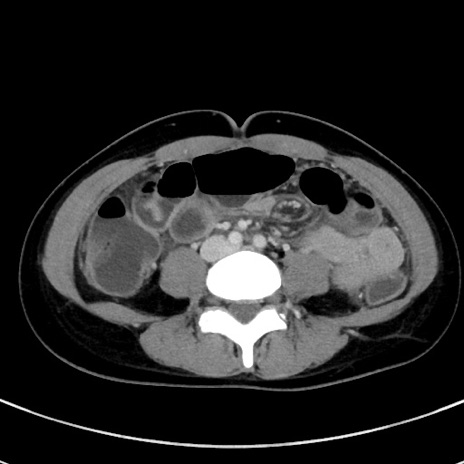

症例17(横断像)

【症例】20歳代女性

【主訴】嘔吐、下腹部痛

【現病歴】昨日夕食後に嘔吐し下腹部痛が出現。本日になっても嘔吐持続し改善しないため来院。

【身体所見】意識清明、BT 37.2℃、BP 108/67mmHg、腹部:平坦、やや硬、下腹部正中から右にかけて圧痛あり、反跳痛軽度あり、tapping pain(+)。

【データ】WBC 13600、CRP 14.94